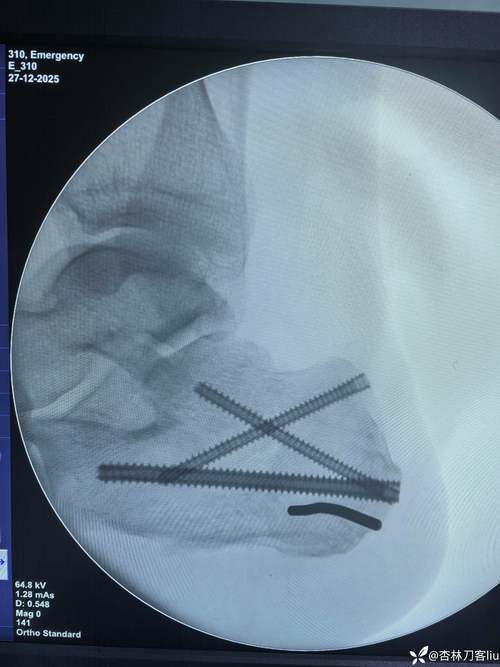

体育资讯3月31日讯 里昂俱乐部官方消息,前锋马利克·福法纳接受了一台右脚踝的小型外科手术,取出了去年10月接受手术时植入体内的骨科固定器械。

2025年10月,马利克·福法纳右脚踝遭遇严重扭伤。